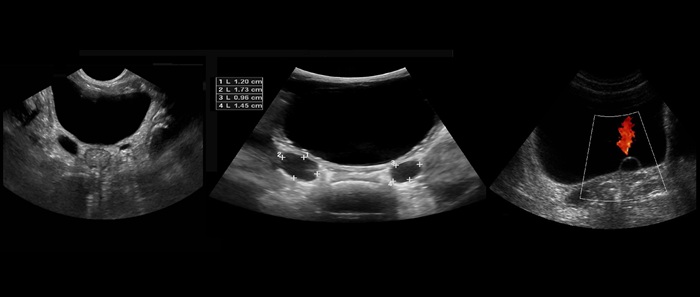

Описание результатов УЗИ почек, мочевого и простаты

После проведения данного вида УЗИ врачом выдается заключение, в котором указываются:

- размеры пузыря, простаты, почек и их физические характеристики;

- особенности эхогенности;

- объем мочевого пузыря и полового органа;

- наличие изменении в структуре ткани.